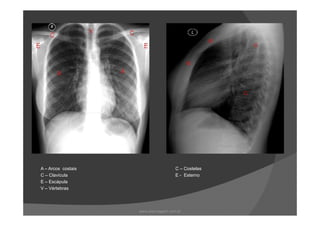

A – Arcos costais C – Costelas

C – Clavícula E - Esterno

E – Escápula

V – Vértebras

A – Arcoscostais C – Costelas C – Clavícula E - Esterno E – Escápula V – Vértebras www.playmagem.com.br